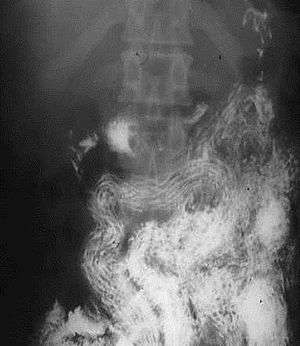

| Ascaris worms (one type of helminth) in the small bowel of an infected person in South Africa (X-ray image with barium as contrast medium) | |